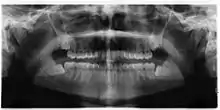

Impacted wisdom teeth are classified by their direction of impaction, their depth compared to the biting surface of adjacent teeth and the amount of the tooth's crown that extends through gum tissue or bone. Impacted wisdom teeth can also be classified by the presence or absence of symptoms and disease. Screening for the presence of wisdom teeth often begins in late adolescence when a partially developed tooth may become impacted. Screening commonly includes a clinical examination as well as x-rays such as panoramic radiographs.

If the tooth cannot be assessed with clinical exam alone, the diagnosis is made using either a panoramic radiograph or cone-beam CT. Where unerupted wisdom teeth still have eruption potential several predictors are used to determine the chance of the teeth becoming impacted. The ratio of space between the tooth crown length and the amount of space available, the angle of the teeth compared to the other teeth are the two most commonly used predictors, with the space ratio being the most accurate. Despite the capacity for movement into early adulthood, the likelihood that the tooth will become impacted can be predicted when the ratio of space available to the length of the crown of the tooth is under 1.[5]: 141

Screening

There is no standard to screen for wisdom teeth. It has been suggested, absent evidence to support routinely retaining or removing wisdom teeth, that evaluation with panoramic radiograph, starting between the ages of 16 and 25 be completed every 3 years. Once there is the possibility of the teeth developing disease, then a discussion about the operative risks versus long-term risk of retention with an oral and maxillofacial surgeon or other clinician trained to evaluate wisdom teeth is recommended. These recommendations are based on expert opinion level evidence.[19] Screening at a younger age may be required if the second molars (the "12-year molars") fail to erupt as ectopic positioning of the wisdom teeth can prevent their eruption. Radiographs can be avoided if the majority of the tooth is visible in the mouth.